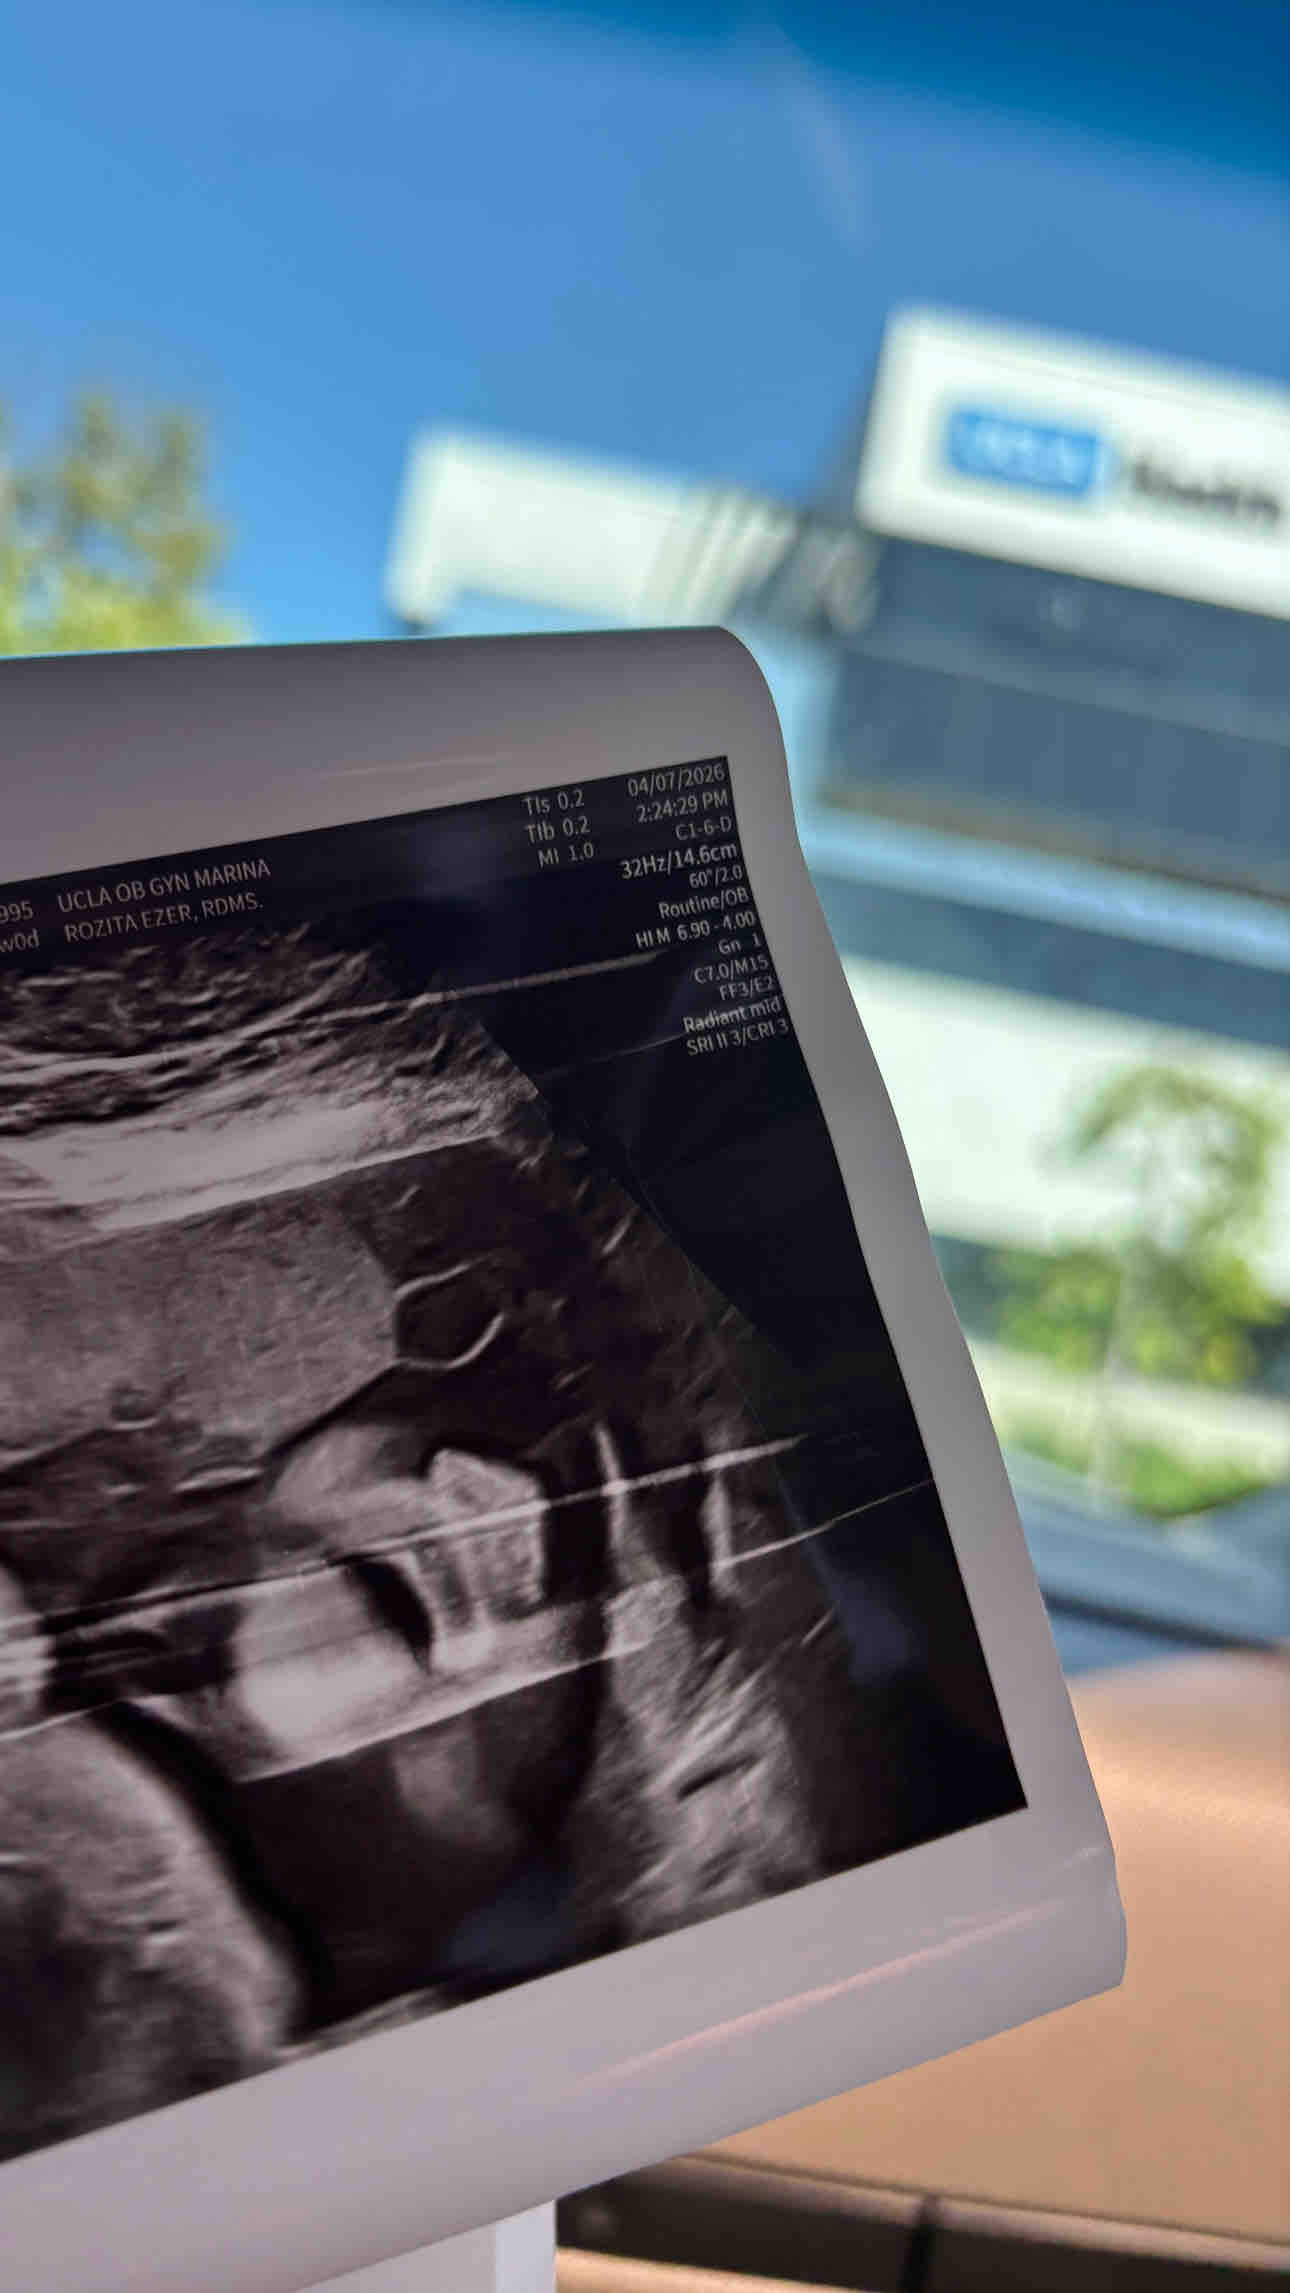

Hello friends and family. Our son has a rare lung lesion called CPAM, which could potentially affect his airway. At 23 weeks gestation, I had to switch OB’s and care team from Bakersfield to Los Angeles for better treatment options. Consequently, I will need to stay in Los Angeles for some time before and after birth, especially if he requires surgery. In light of these circumstances, we kindly request any assistance you can provide to cover the costs associated with our stay, including food, gas, and other expenses. Your support means the world to us as we care for our precious baby boy. We truly appreciate your generosity and compassion. Thank you from the bottom of our hearts. God bless